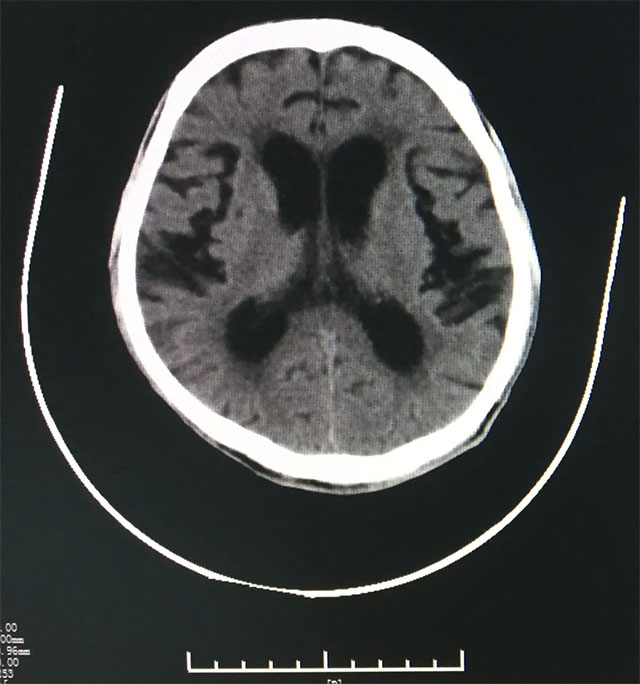

三、该病患经影像学查体显示:患者脑室增大,周边有间质性水肿,不符合PD影像表现。

对于从业经验丰富、医学造诣深厚的张静波主任来说,她诊断老罗患有“正常压力脑积水”,因为只有罹患该种疾病,老罗具备如二便障碍,走路不稳,记忆力下降,计算力差,言语欠流畅,四肢共济失调等正常颅压性脑积水等临床表现,同时影像学也符合正常颅压性脑积水。有了这些依据,仍然不能确诊,临床还需要腰穿做脑脊液放液试验才能确诊。

▲ 影像医学显示患者脑室增大